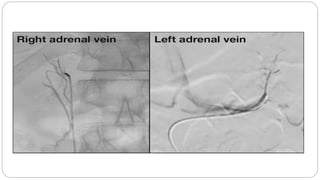

Adrenal vein sampling (AVS)

 AVS is a safe and valuable tool for differentiation between unilateral

and bilateral cortisol secretion

 It may not correlate with CT findings

 It could detect unvisualized adrenal mass

 It should be considered when operative treatment will be utilized